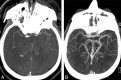

A, CTA showing occlusion of distal right M1 MCA. Poor contrast opacification of pial arteries even on the normal side (left) makes estimation of leptomeningeal collateral status difficult. B, Greater contrast opacification of the ipsilateral basal vein of Rosenthal than the MCA in a patient with occlusion of the distal left M1 MCA. Delayed triggering as evidenced by excessive venous contamination can result in overestimating collateral status.